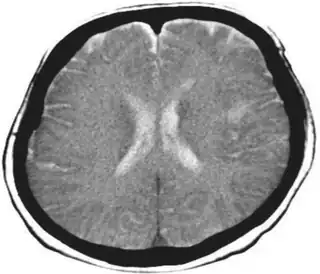

Diagnosis may be clinical if associated with dementia and other etiologies. In cases caused by stroke, MRI will show a corresponding stroke in the inferior parietal lobule. In the acute stage, this will be bright (restricted diffusion) on the DWI sequence and dark at the corresponding area on the ADC sequence.